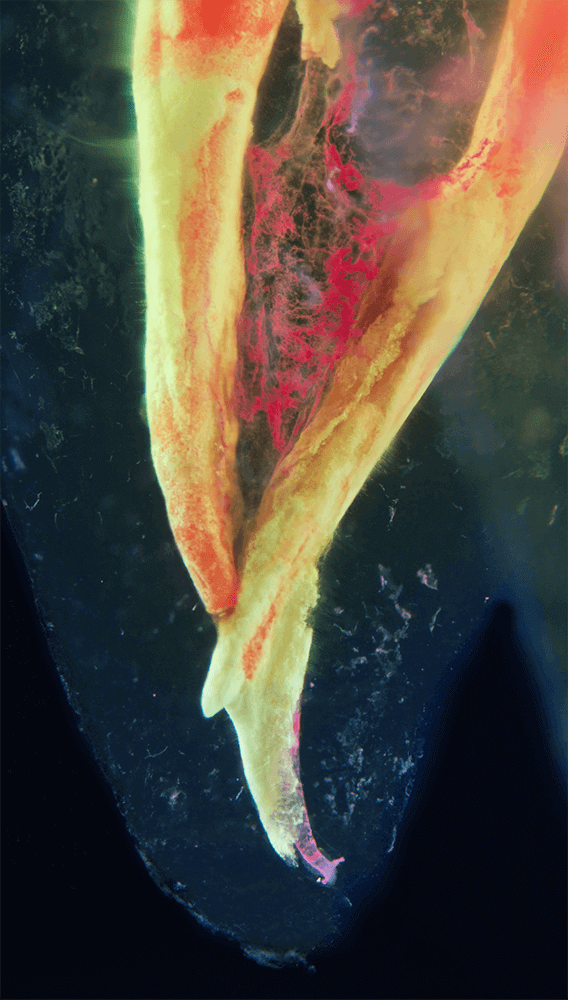

Transparente Zahnpräparate

Bilder transparenter Zahnpräparate

Das Verfahren, Zähne in durchsichtige Präparate zu überführen ist schon über 100 Jahre alt. Aber erst durch die Weiterentwicklung der alten Technik und die Kombination mit moderner Fotografie sowie der Entwicklung eines geeigneten Gefäßes zur Fotografie ist es meinem Vater Dr. Holm Reuver gelungen, einzigartige Bilder vom Inneren der Zähne aufzunehmen.

Die Bilder sind in verschiedenen Größen wählbar und auch als POPART-Variante erhältlich. Sie sind hervorragend geeignet für die Beratung von Patienten vor endodontischen Behandlungen, aber auch ein beliebter Eyecatcher im Wartezimmer. Außerdem haben die Bilder einen bedeutenden Stellenwert für die Erforschung der Pulpatopografie und für die Lehre im Bereich der Endodontie.